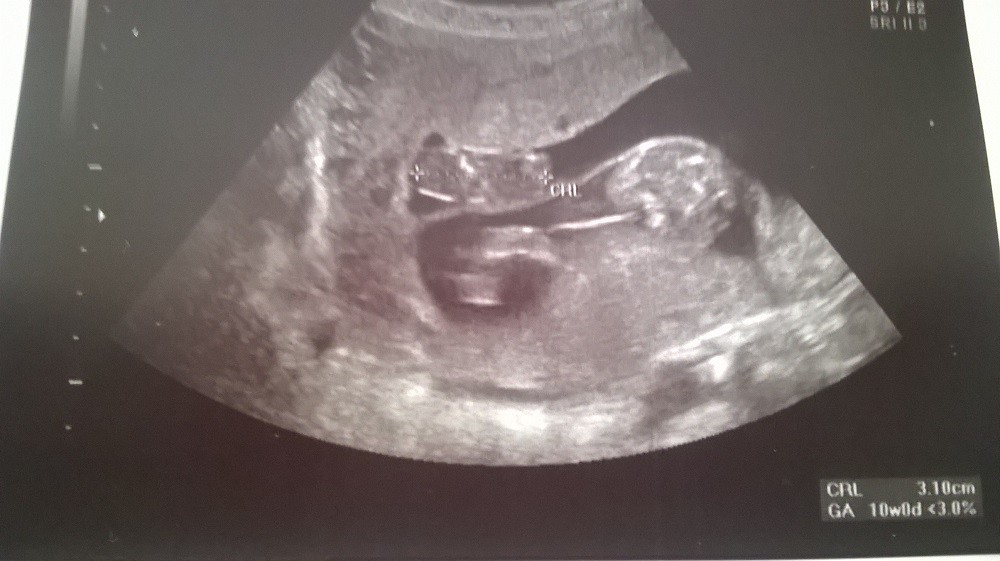

Wróciłam z mieszanymi uczuciami ...łożysko jest bardzo nisko leży na szyjce ...macica jest bardzo obciążona bo z jakichś powodów płyn z worka owodniowego zamiast się kurczyć z aniołkiem to się nadal wypełnia - nie jest w stanie zlokalizować skąd pobiera łożysko ten płyn. Aniołek zmniejszył się nieznacznie ma 3,10 cm - skamieniał więc już nie zniknie. Lekarz martwi się co będzie, gdzie ciśnienie w macicy zacznie rosnąć ...czy zawartość drugiego worka nie pęknie i skąd ten płyn który dodatkowo obciąża mi macicę. Na chwilę obecną na 80% dziewczynka, zdrowa - nie znam wymiarów bo ...no bo są inne problemy. W razie krwotoku, plamień do szpitala mam jechać do Warszawy.

Córcia:

Zobacz załącznik 800517

Nessi, kochana, bedzie dobrze, nie martw sie, acz silna dla swojej córci!!! Ale super, ze dziewczynka :) gratulacje :) bedzie gimnastyczka, tak pięknie sie zgina! :) widziałyśmy to wczoraj na brzuchu, jak ćwiczy wykopy i dzisiaj na usg! :)